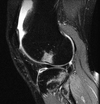

An 18-year-old man sustains a twisting injury to the left knee while playing football. An MRI scan is shown in Figure 48. What is the most likely diagnosis?

MRI scan shows a displaced, bucket-handle lateral meniscus tear. The sagittal view shows the typical “large anterior horn” sign, or “double meniscus” sign in which the displaced bucket-handle fragment appears just anterior to the native anterior horn of the lateral meniscus. The presence of the fibula on the sagittal view confirms this as the lateral compartment. The image is lateral and the cruciate ligaments are not visualized. The articular cartilage shown does not demonstrate an osteochondral lesion.